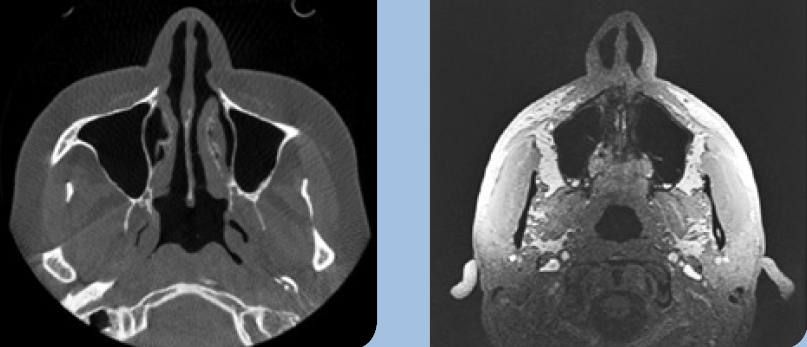

- Die Computertomographie (CT) ist nach wie vor das am häufigsten angewendete Verfahren. Die Vorteile liegen in einer guten Darstellung der Tumorläsion, des umgebenden Weichgewebes und der möglichen Knocheninfiltration. Andrle et al. konnten feststellen, dass die Computertomographie eine hohe Spezifität in der Erkennung von Knocheninfiltration aufweist (Quellenangabe). Ebenso weist die CT eine hohe Sensitivität in der Erkennung von besonders kleinen Arealen der Knocheninfiltration auf [7]. Nachteile der CT sind die geringere Auflösung, die hohe Strahlenbelastung sowie die ausgeprägten Metallartefakte, wie z. B. bei metallischen Restaurationen.

- Die digitale Volumentomographie (DVT) liefert die höchste Auflösung von knöchernen Strukturen, die Darstellung und/oder Differenzierung von Weichgewebe ist jedoch nicht möglich. Vorteile sind die geringen Kosten und die im Vergleich zur CT reduzierten Metallartefakte. Nachteilig hingegen sind der geringe Weichteilkontrast und die Gewebedifferenzierung (Abb. 2 u. 3).

- Die Magnetresonanztomographie (MRT) liefert den besten Weichgewebekontrast. Dies macht sie besonders sensitiv in der Detektion von kleinen, im Frühstadium befindlichen Mundhöhlenkarzinomen. Die MRT weist eine hohe Spezifität und geringe Sensitivität in der Beurteilung der Knocheninfiltration auf. Vorteile sind die fehlende Strahlenbelastung sowie die geringe Ausprägung von Metallartefakten. Nachteile sind der Geräuschpegel, die lange Scandauer und die damit verbundene Gefahr von Bewegungsartefakten (Abb. 4 u. 5).